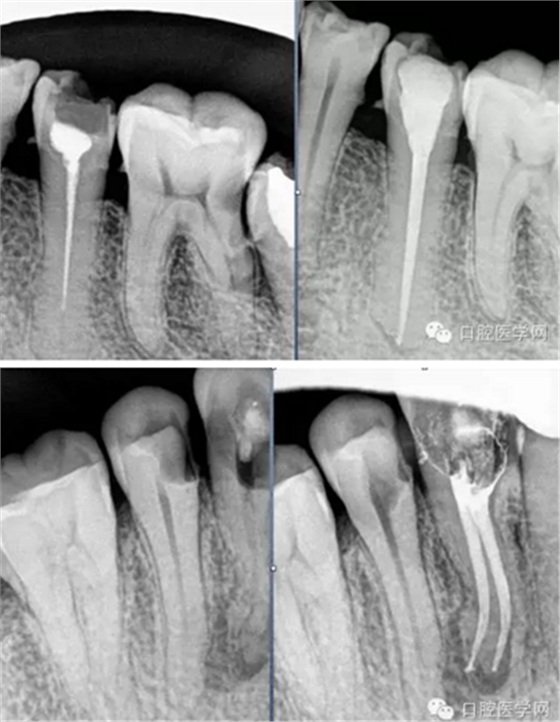

試尖(檢查是否恰填)

根充(從術(shù)后X光片可以看出根管充填完整,專業(yè)上叫恰充)

根充其實(shí)很簡單,只要前面的預(yù)備做好了,后面的充填就很順利,試尖恰好,AH樹脂湖劑+大準(zhǔn)度牙膠充填,平齊根管口將牙膠截掉,冷充的話就結(jié)束了。若要做熱充,將攜熱器頭對準(zhǔn)牙膠的中央,加熱3-4秒迅速壓入需要截?cái)嗟牟课唬缓蟮仁畮酌氪龜y熱器桿冷卻后再加熱1-2秒取出牙膠,最后將熱牙膠注入,邊注邊壓,嚴(yán)密充填,結(jié)束。暫封一周后冠修復(fù)。通過這樣的操作牙齒就不可能發(fā)生再次感染和疼痛了。

常用標(biāo)準(zhǔn):恰充,三維致密,流暢,錐度流暢一致。